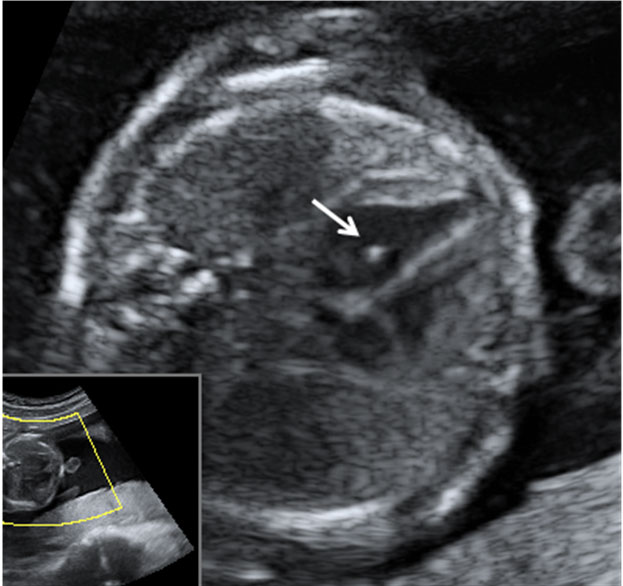

Corazón fetal en el que se aprecia una mancha brillante o foco ecogénito

La imagen de la flecha indica el foco ecogénito en el ventrículo izquierdo.